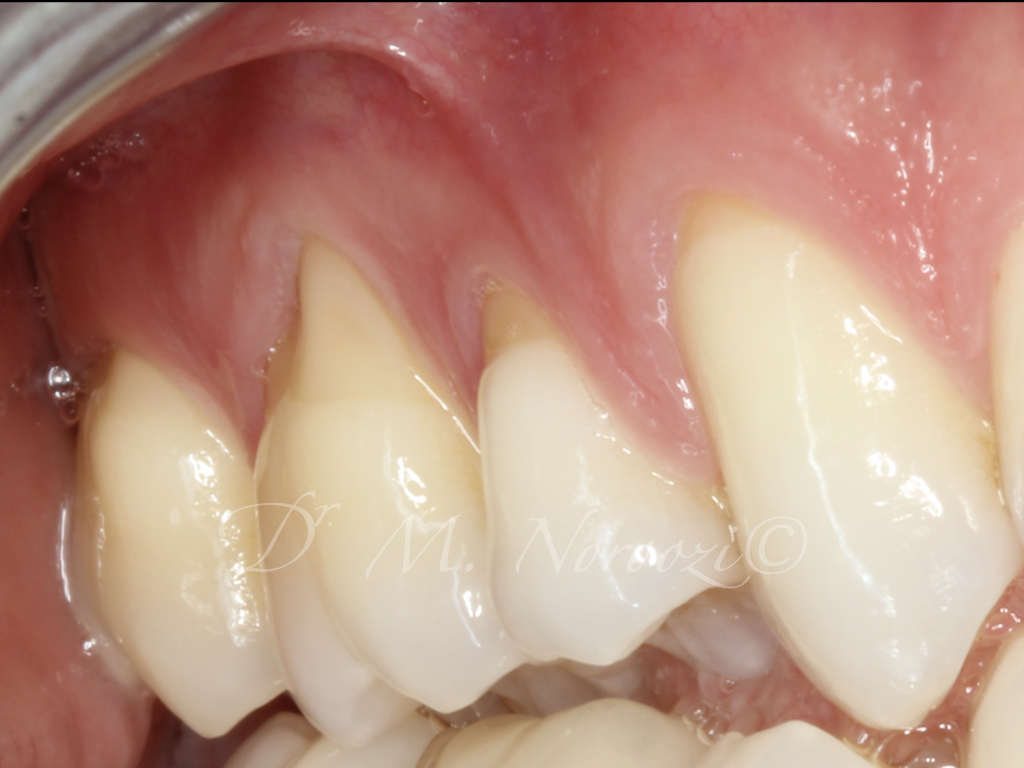

Connective Tissue Gingival Grafting for Gingival Recession